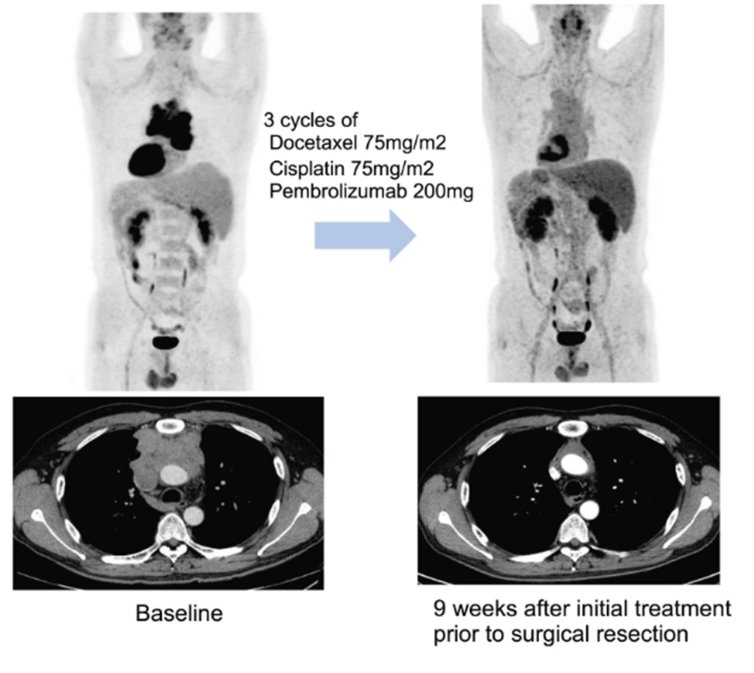

연구팀은 이들 환자에게 3주 간격으로 세 번에 걸쳐 기존 항암화학요법에 펨브롤리주맙을 병용 투여한 다음 수술 가능 여부를 평가했다.

연구팀에 따르면 추적관찰 기간 27.5개월(중앙값) 동안 전체 환자의 57.5%(23명)에서 수술 전 치료를 통해 종양의 크기가 유의미하게 감소하는 반응을 보였다. 또 82.5% 환자에서는 해당 치료로 인해 질병의 진행이 억제 되는 질병 조절이 관찰됐다.

수술을 받을 만큼 암이 줄거나 반응을 보인 덕분에 전체 환자의 70%(28명)가 수술을 받았다

치료 결과 병리 검사를 통해 암세포가 10% 이하로 감소한 지를 평가(MPR)했을 때 전체 환자의 32.5%(13명)가 도달한 것으로 나타났다.

당초 기대치 50%에는 미치지 못했지만, 수술 환자 놓고 보면 MPR 도달 비율은 46.4%로 증가해 펨브롤리주맙이 흉선상피종양 치료 선택지에 포함될 가능성에 파란불이 켜졌다.